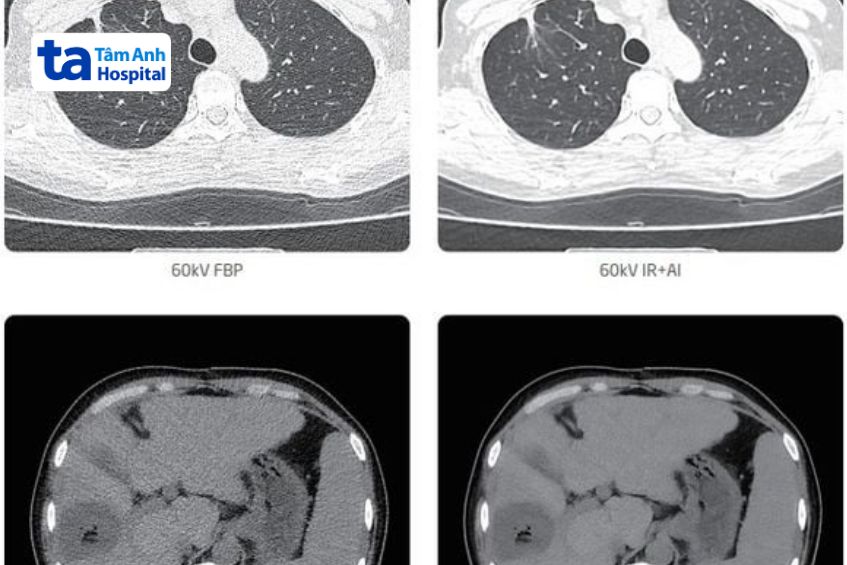

Hiện nay, nhờ vào sự phát triển của y học hiện đại, kỹ thuật chụp CT không chỉ dừng lại ở 32 lát cắt mà đã được phát triển lên đến 64, 128, 256, … lát cắt với hiệu quả khảo sát thương tổn cao, hỗ trợ bác sĩ chẩn đoán bệnh lý chính xác. Không những vậy, Bệnh viện Đa khoa Tâm Anh TP.HCM hiện đang ứng dụng hệ thống chụp CT 256 dãy đầu dò tích hợp trí tuệ nhân tạo hiện đại nhất, lần đầu tiên có mặt tại Việt Nam.

Kỹ thuật chụp CT có số dãy (lát cắt) càng cao thì càng giúp thu nhận được nhiều hình ảnh chụp cắt lớp và phần mềm xử lý hình ảnh có chất lượng cao, ổn định hơn. So với chụp CT 16 dãy, hệ thống chụp CT 32 dãy sở hữu nhiều ưu điểm vượt trội hơn như tốc độ quét cao hơn, các lát cắt hình ảnh mỏng và khít nhau hơn.